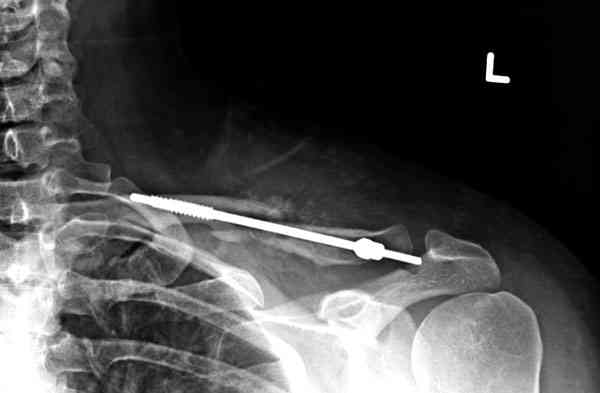

Судя по проекциям ключицы, очевидно разобщение фрагментов, чаще всего сопровождающееся интерпозицией платизмой. для 15 летнего пациента, категории физически активных пациентов выбрал бы оперативный метод( интрамедуллярно

винтом с частичной резьбой).

Для выбора метода лечения перелома ключицы при первичном обращении рутинно необходимо выполнение Рг графии в двух проекциях. принимать решение о

тактике лечения перелома, руководствуясь только одной передне-задней проекцией ошибочно( почему-то в отношении ключицы подобная недооценка

перелома наиболее часто встречается).

При выборе тактики лечения перелома ключицы всегда желательно иметь две взаимоперпендикулярные проекции: если фрагменты находятся в контакте друг с другом - лечение консервативное( достаточно косыночной повязки и спать с разведенными плечами на подушке между лопаток), разобщены - хирургия. Можно ждать 8-10 недель и импровизировать с кольцами, рамкой Чижина в это время - кому как удобно, я бы не стал.